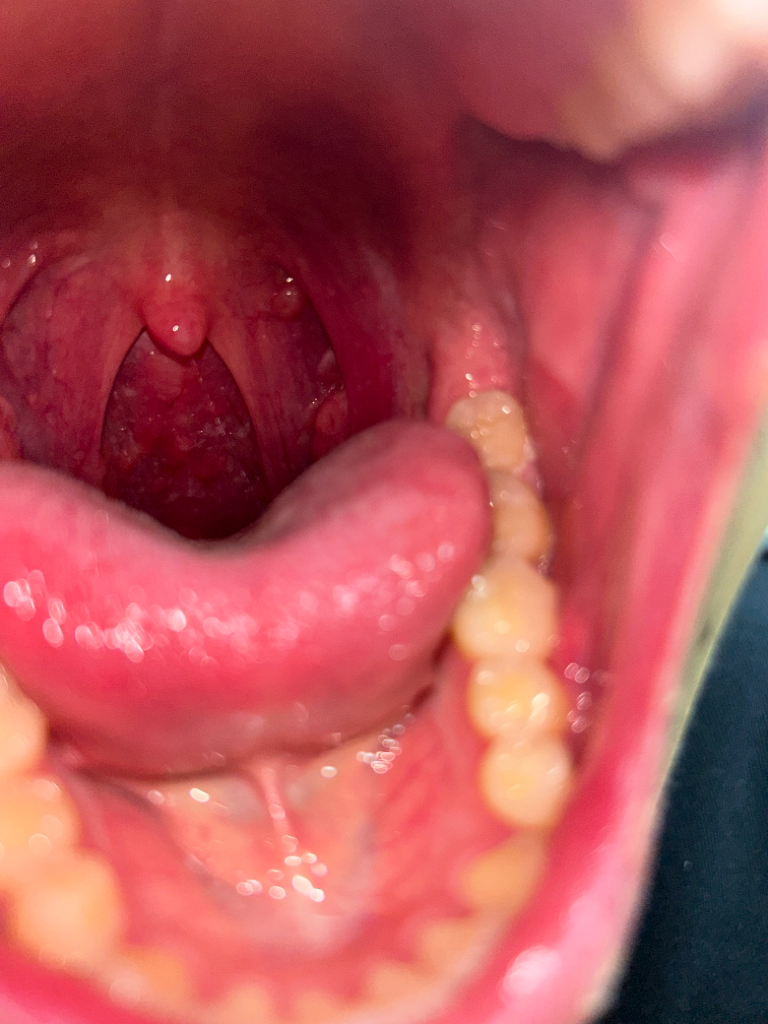

목에 이물감이 들고 침 삼키는게 불편해요

어느날부터 목에 이물감이 들고 침을 삼키는 게 불편해요 또 목구멍? 혀가 끝나는 지점하고 목구멍 쪽에 뭐가 오돌도톨한게 생겼어여 그리고 목에 자꾸 가래가 끼는듯한 느낌이 들어요 추가적으로 침에서 일반적인 침 냄세보다 조금 더 신 냄세가 나는 것 같아요 마지막으로 상관이 있을지는 모르겠지만 코로 숨쉬는게 많이 불편해요 ㅠㅠ

• 1번 째 사진

오돌토돌하다고 말씀하신 부분은 정상적인 림프조직인데, 인후통과 냄새가 사라지지 않아 고민이시라면 가까운 이비인후과를 방문해보시기를 권해드립니다.